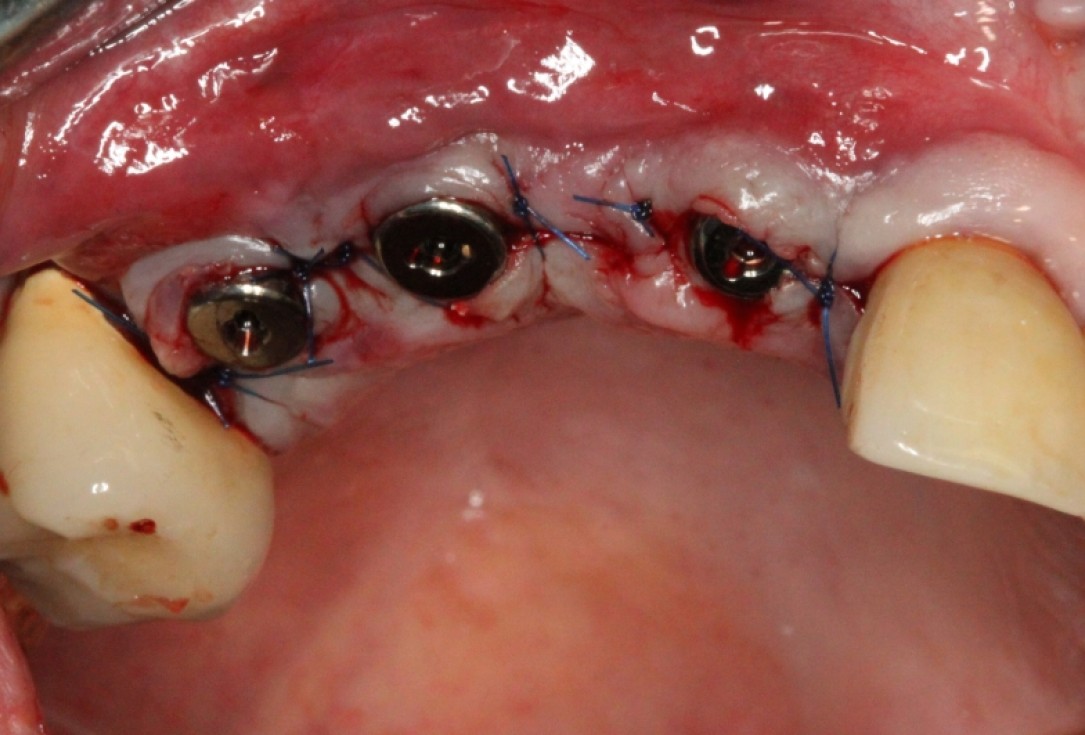

Three implants placed in a narrow posterior mandible